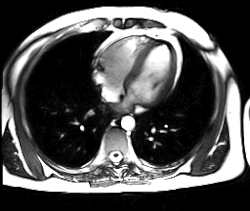

Современные технологии и внедрение компьютерной техники обусловили возникновение такого метода, как виртуальная эндоскопия, который позволяет выполнить трёхмерное моделирование структур, визуализированных посредством КТ или МРТ. Данный метод является информативным при невозможности провести эндоскопическое исследование, например, при тяжёлой патологии сердечно-сосудистой и дыхательной систем. Метод виртуальной эндоскопии нашёл применение в ангиологии, онкологии, урологии и других областях медицины.